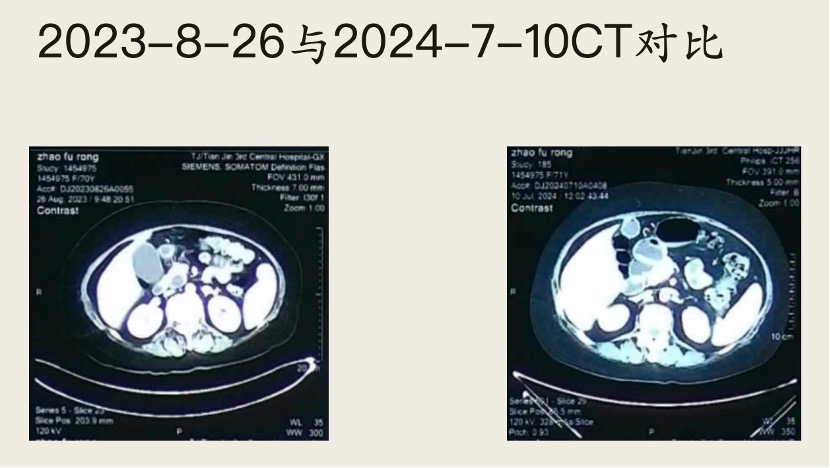

三年前,天津的赵阿姨查出胰腺癌,由于阿姨患有20多年的糖尿病,她没有选择手术治疗,而是直接找到刘鲁明教授接受中医治疗。

没想到的是,经刘鲁明教授团队治疗仅3个月后,再做强化CT复查,肿瘤已经消失不见了!现在的赵阿姨,胃口好了,体重也增加了,已经可以像普通老人一样正常生活。

(图三为治疗五个月后,肿瘤消失影像)